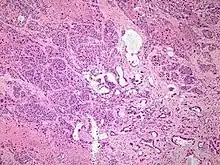

| Micrograph of an adenosquamous carcinoma of the lung. The adeno- or glandular component is on the left of the image and the squamous component on the right of the image. H&E stain. | |

Light microscopy shows a combination of gland-like cells and squamous epithelial cells.[4] On immunohistochemistry, it is typically positive for CK5/6, CK7 and p63, and negative for CK20, p16 and p53. On genetic testing, KRAS and p53 are typically altered.[4]